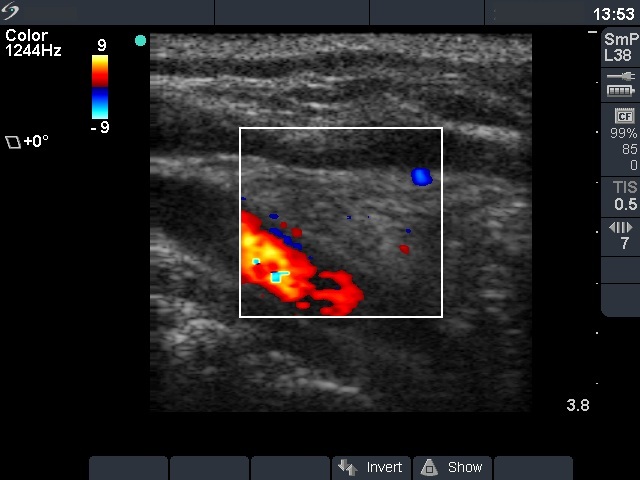

The role of complex diagnosis - oxyphilic lesions - Case 6. (ultrasonographic picture 3)

Right lobe, longitudinal scan. As in most cases of an atrohic phase of Hashimoto's thyroiditis the thyroid is avascular.